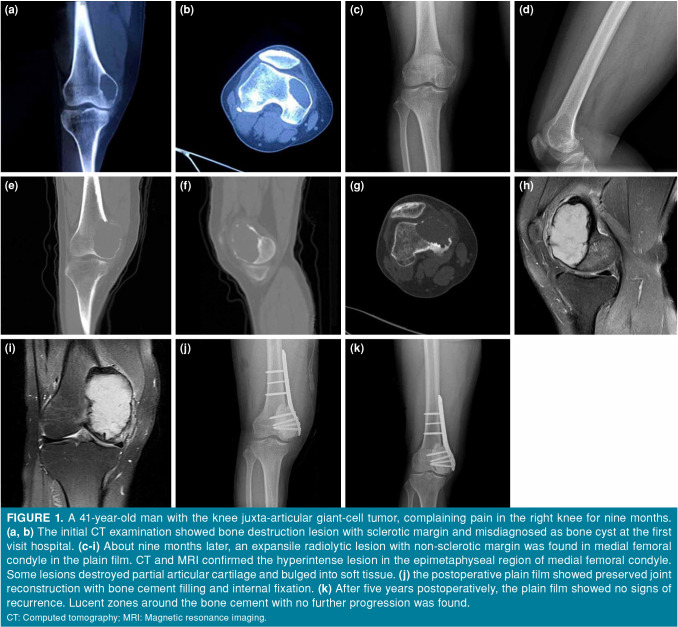

Objectives: This study was to evaluate the radiological and clinical outcomes of patients with juxta-articular giant-cell tumors (GCTs) around the knee treated with bone cement filling and internal fixation after extensive curettage.

Patients and methods: A total of 15 patients (6 males, 9 females; mean age: 35.3±8.4 years; range, 24 to 53 years) with juxta-articular GCTs around the knee were retrospectively reviewed between January 2010 and June 2020. Wound healing, functional status as assessed by the Musculoskeletal Tumor Society (MSTS) scores, local recurrence, metastasis, and complications were evaluated.

Results: The mean follow-up was 41.3±9.9 (range, 24 to 69) months with an overall survival of 93.3%. The mean distance between tumor and cartilage was 6.29±3.73 mm. Five patients underwent reconstruction with cancellous allografts and the mean distance between tumor and cartilage was 2.20±1.48 mm in these patients. At the final follow-up, three patients had Kellgren-Lawrence Grade 2 tibiofemoral osteoarthritis in the operated knee. Lucent zones around the bone cement with no further progression were found in five patients. One patient experienced recurrence 17 months after surgery and was treated by en-bloc resection and reconstructed with a tumor endoprosthesis. The remaining 14 patients had a mean MSTS score of 26.86±2.11 (range, 23 to 30) at the final follow-up. The mean overall range of motion at the final follow-up was 109.20±14.20° (range, 85 to 130°).

Conclusion: Bone cement filling and internal fixation after extensive curettage is a viable strategy for accessing juxta-articular GCTs around the knee. The choice of local adjuvants, subchondral bone grafting, and the thickness of subchondral bone require more attention to preserve the continuity of articular cartilage.